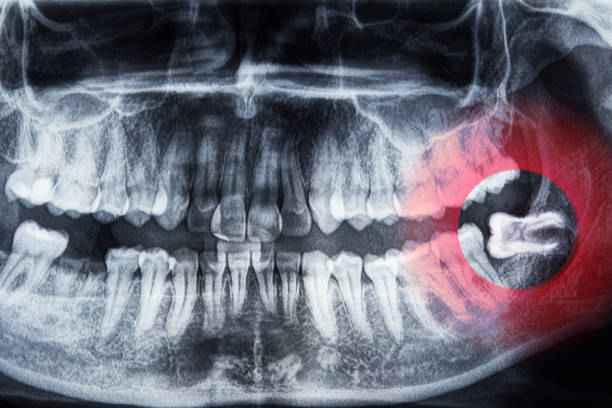

كيف يتم إجراء جراحة ضرس العقل؟

تُعد جراحة ضرس العقل إجراءً طبيًا دقيقًا يُجرى عندما يفشل الضرس في البزوغ بشكل طبيعي أو يتسبب في آلام ومضاعفات مستمرة.

1. تبدأ العملية عادةً بتقييم شامل لحالة الفم باستخدام الأشعة السينية لتحديد موضع الضرس واتجاهه وعمق جذوره.

2. بعد ذلك يتم تخدير المنطقة تخديرًا موضعيًا، وقد يُلجأ إلى التخدير الكلي في الحالات المعقدة أو عند وجود أكثر من ضرس مطمور.

مضاعفات ضرس العقل المدفون أو المتأثر

يُعد ضرس العقل المدفون من أكثر الحالات تعقيدًا في طب الأسنان، إذ يبقى محاصرًا داخل العظم أو اللثة. هذا الوضع يُنتج اعراض ضرس العقل بشكل أكثر حدة، وقد يسبب مضاعفات متعددة، منها:

• تكوّن أكياس عظمية قد تتطور إلى أورام حميدة.

• التهابات عميقة يصعب علاجها دوائيًا.

• ضغط مستمر على الأعصاب المجاورة.

• تنميل أو وخز في الفك أو الشفاه.

• تضرر جذور الأسنان المجاورة.

• صعوبة في فتح الفم أو تحريك الفك.

هذه المضاعفات تجعل التدخل الطبي ضرورة لا خيارًا.